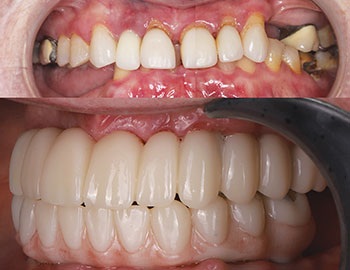

Our patient, a healthy woman in her early 60s, presented with a terminal dentition (Fig. 1) in both arches, collapsed bite, unstable occlusion, midline shift, asymmetric horizontal plane and bone loss (Fig. 2). She was looking for a fixed solution that would give her the confidence to smile, eat and socialize without restrictions. Several previous treatment plans suggested placing provisional dentures as an interim until the implant stabilized, which did not resonate with her desires during the healing phase.

Fig. 1

Fig. 2

Final seating: Perfect fit, zero adjustments

Final delivery day could not have gone smoother. No adjustments were needed—a testament to precision planning and execution along with digital workflows. Patient satisfaction was beyond expectations—she could floss between her teeth, enjoy a natural smile and eat comfortably. The occlusion was balanced and aesthetics were on point, and the patient left with tears of joy (Figs. 15–17).